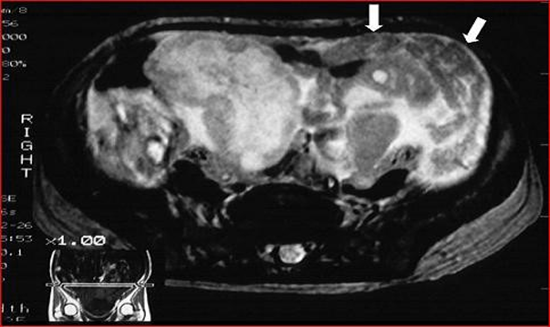

The ultrasonographic study shows two large masses, one in the left pelvic portion and the other in the right pelvic portion.

The masses appear homogeneous and slightly echogenic with small cystic areas around the periphery. There is a small amount of free fluid in the pelvis (Figure 3).

Figure 3: Transverse ultrasound shows a well-defined, homogeneous and hyperechoic mass, with focal cysts at the periphery (white arrows) and a small amount of free fluid (black arrow).